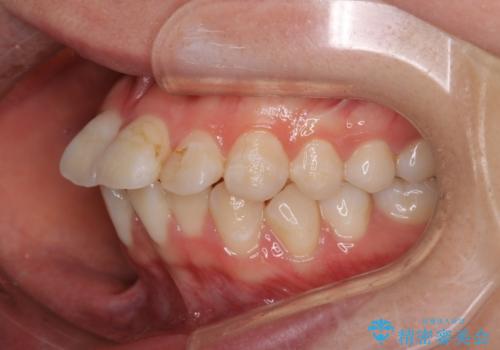

- 前歯のがたつきと口元を気にされて来院されました。

上下4番目の歯を抜歯してがたつきを改善しながら口元を下げる治療計画を立てました。

抜歯矯正をして口元を下げたことで、口元が下がりEラインが大変綺麗になりました。

矯正期間も1年9ヶ月と比較的短期間で終了することができました。